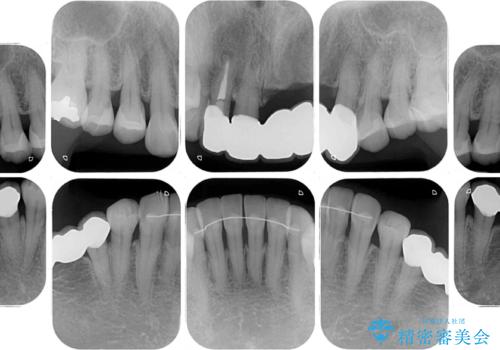

- 前歯の歯肉の腫れを気にして来院された患者様です。

前歯のみならず、奥歯の銀歯や下顎前歯のデコボコなど、色々と気になる部分を治したいとのことでした。

前歯は抜歯が必要であったので、抜歯を行い、その後歯肉移植をおこなった上でオールセラミックブリッジによる補綴治療を行うこととしました。

下顎と上顎臼歯部については矯正治療を行い、奥歯の欠損部位はオールセラミックブリッジを、その他の銀歯はセラミックインレーなどにより治療を行うこととしました。